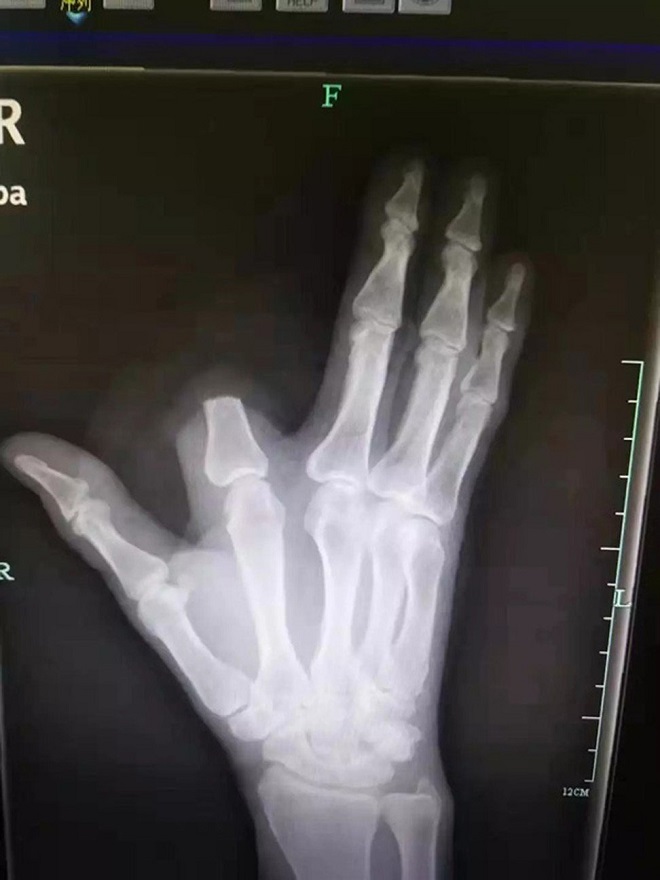

Các bác sĩ đã không thể nối lại ngón tay cho nạn nhân. Ảnh: Weibo. |

Tuy nhiên, người đàn ông đã để ngón tay bị cắt cụt trên sườn núi, điều đó có nghĩa là các bác sĩ sẽ không có cơ hội gắn lại cho ông.

Yuan Chengda, một bác sĩ khác của bệnh viện, cho biết thật đáng tiếc khi ông Zhang không thể giữ lại ngón tay. Việc cắt đứt là không cần thiết.